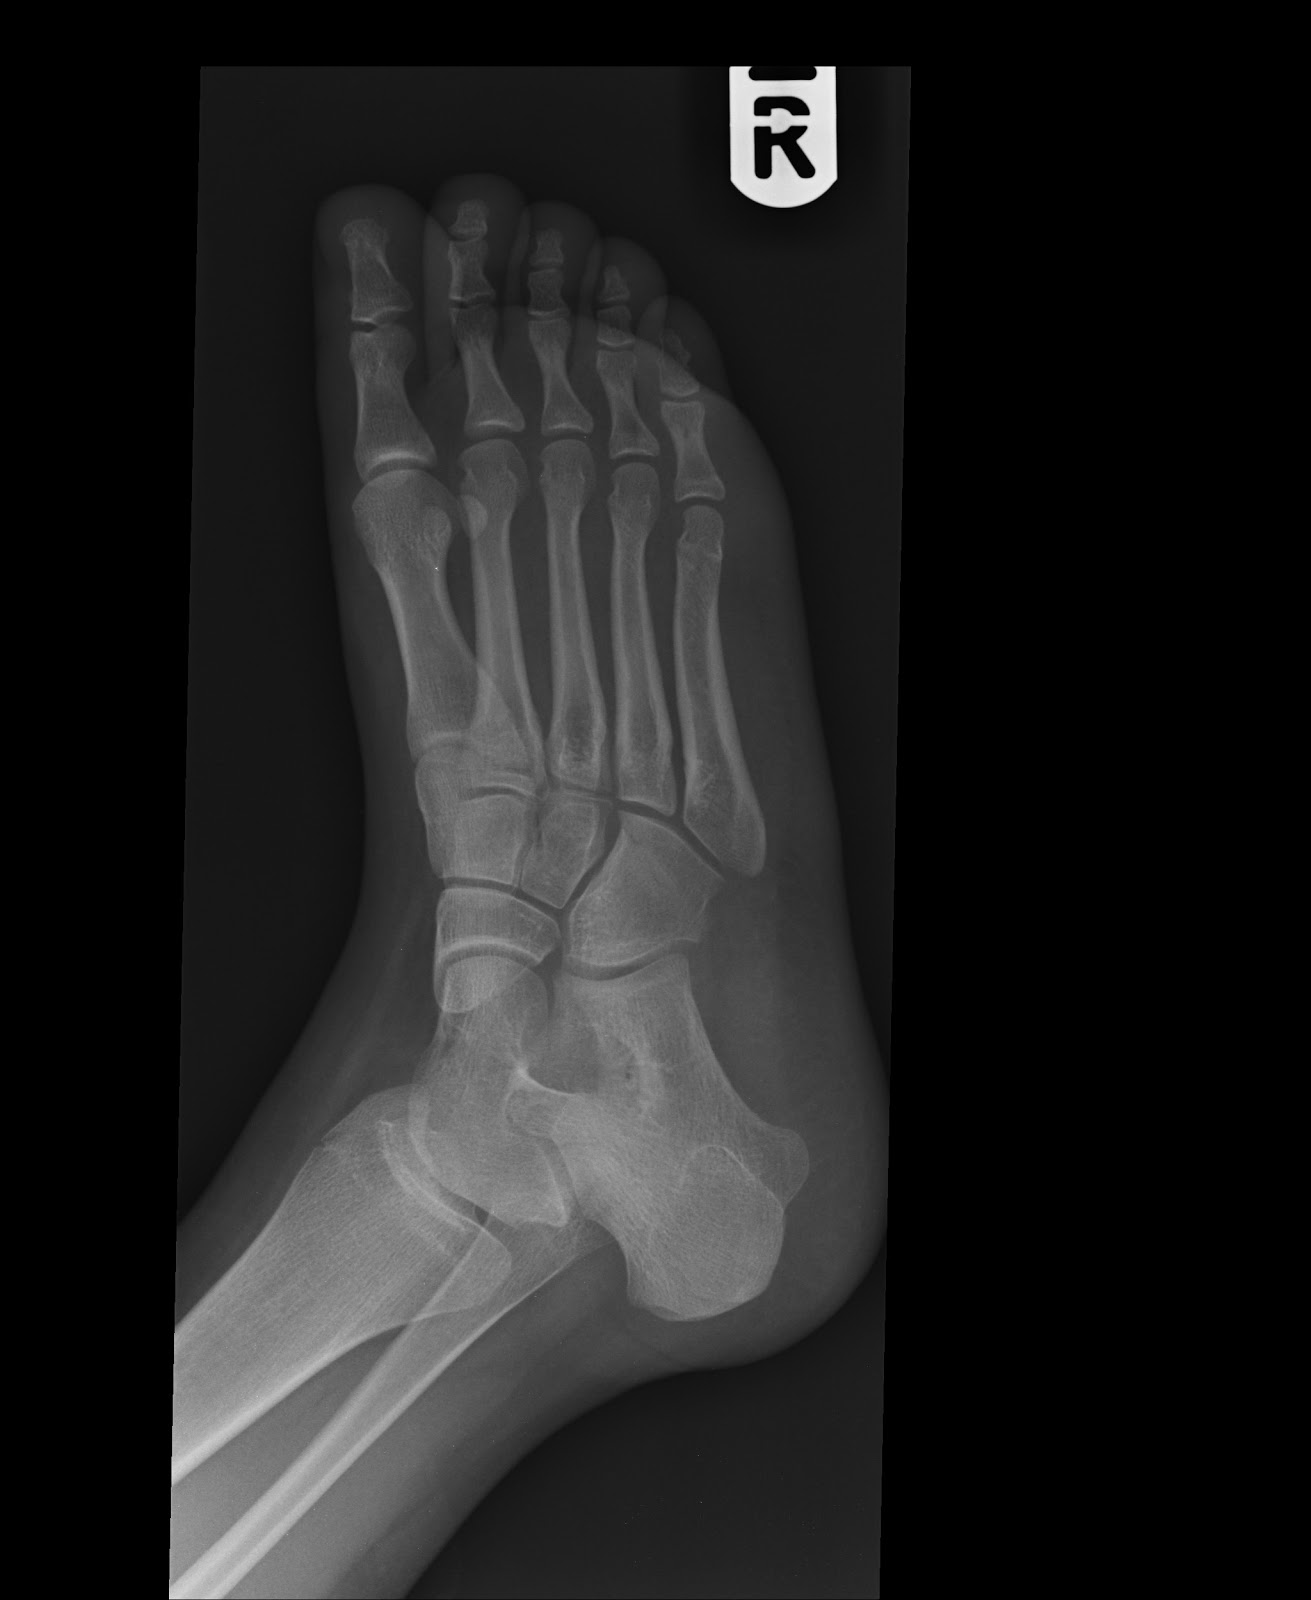

Avulsion fracture of the cuboid Image

Cuboid Avulsion Fracture

Avulsion fracture of the dorsal cuboid bone Image

Cuboid fractures due to the particular bone anatomy and its protected location in. the midfoot are rare, and they are usually associated with complex injuries of the. foot. Clinical examination to.. Cuboid fractures can be the result of bone injury due to compression after a car accident or direct crush of the lateral aspect of the dorsum of the foot as it may happen after a heavy object falls on the foot.. Avulsion fractures are treated with protected weight bearing as tolerated and a fracture boot for 4 to 6 wk. These fractures.